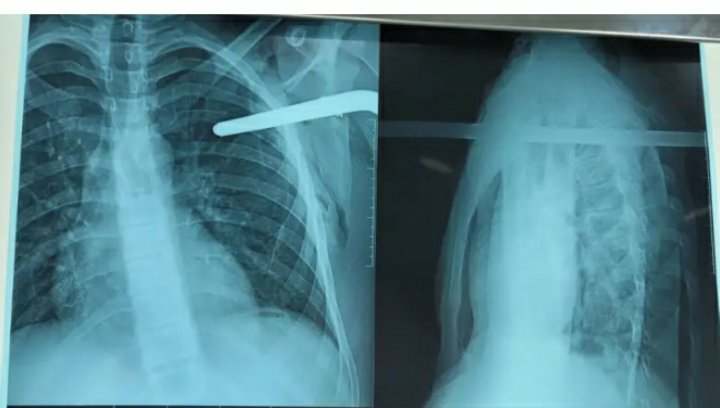

تمكن الطاقم الطبي في مستشفى مطفى باشا بالعاصمة، ليلة أمس الجمعة، من إنقاذ مراهق اخترقت قطعة حديدية صدره.

وحسب بيان لصفحة المستشفى على فايسبوك، تعرض شاب يبلغ من العمر 16 سنة ينحدر من مدينة سور الغزلان بالبويرة، لحادث مؤلم، حيث إخترق قضيب حديدي جانبه الأيسر من الصدر بعد سقوطه من سطح المنزل.

مما إستلزم رجال الحماية المدنية بقطع القضيب ونقله معه إلى المركز الإستشفائي الجامعي مصطفى باشا، حيث تم التكفل به في مدة قياسية وحالته الصحية مستقرة.

وقام بالعملية الطاقم الطبي لجراحة الصدر والأوعية الدموية بالتعاون مع مصلحة العظام والرضوض وأخصائيي التخذير والإنعاش والطاقم الشبه طبي لمصلحة الإستعجالات الجراحية.